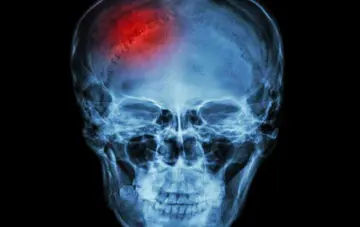

ابداع روش نوین درمانی و افزایش طول عمر و کیفیت زندگی مبتلایان به تومور مغزی بدخیم

رییس دانشگاه علوم پزشکی شهید بهشتی خبر از افزایش طول عمر و کیفیت زندگی بیماران مبتلا به تومور بدخیم مغزی با ابداع روشی نوین برای نخستین بار در جهان توسط متخصصان جراح مغز و اعصاب و ستون فقرات این دانشگاه داد.